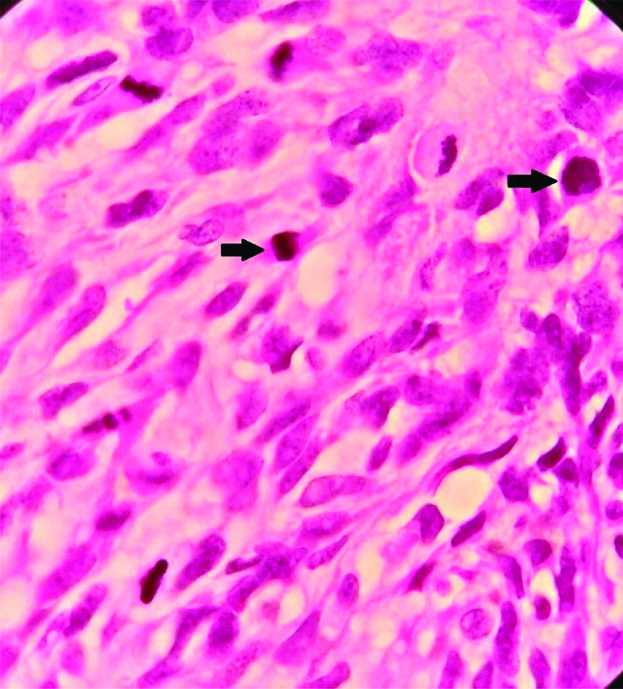

Out of 108 cases analysed, 102 cases (94.4%) shows low to moderate atypia, 63 cases (58%) showed haemorrhage, 60 cases (55.6%) showed inflammation, 5 cases (4.7%) showed necrosis, 36 cases (33.3%) showed myxoid change, 33 cases (30.6%) had perinuclear vacuoles, nine cases (8.3%) had skenoid fibres, six cases (5.6%) had multinucleation and mucosal invasion. Out of the nine variables analysed, only necrosis was found to have significant association with high risk group. A total of 63 cases (58.4%) of cases shows ≤5 mitosis/50 HPF and 45 cases (41.6%) of the cases showed >5 mitosis/ 50 HPF. Atypical mitotic figures are depicted in [Table/Fig-3]. A total of 97 cases (90%) of the tumours with size less than five cm was in the low risk category. A total of 59 cases (54.5%) tumours with the size in the range of 5-10 cm and 95 cases (87.5%) with size of >10 cm were in high risk category. A total of 101 cases (93.3%) of the tumours in the high risk category had >5 mitosis per 50 HPF concluding that the tumour size >5 cm and mitotic rate >5/50 HPF are indicators of worse prognosis.

Microphotograph depicting atypical mitosis (H&E, X 1000).